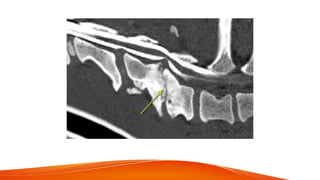

• Atlanto axial instability - subluxation of joint in small toy breeds

Hyperpathia , quadriplegia , respiratory arrest

• Congenital form - improper embryologic development of odontoid process

• Traumatic form - Bending force & displacement to cervical region

Translational & articular displacement of joint